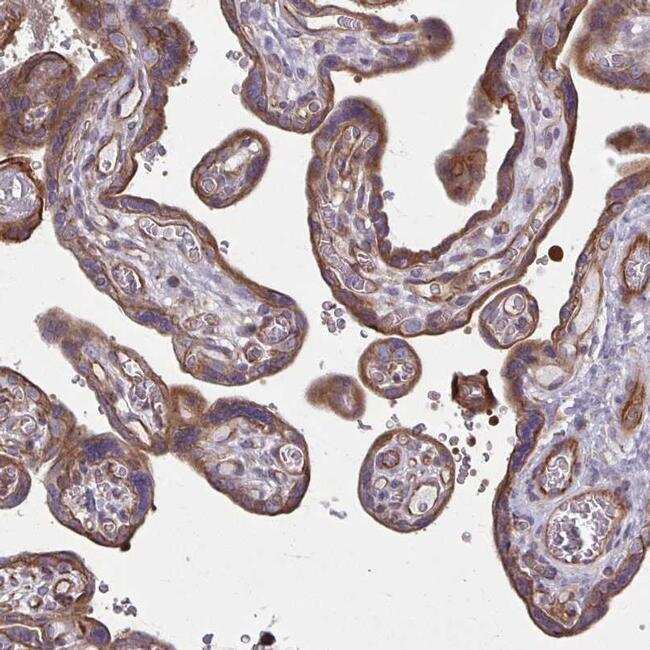

- Immunohistochemical analysis of EID2B in human placenta using EID2B Polyclonal Antibody (Product # PA5-64159) shows strong membranous and cytoplasmic positivity in trophoblastic cells.